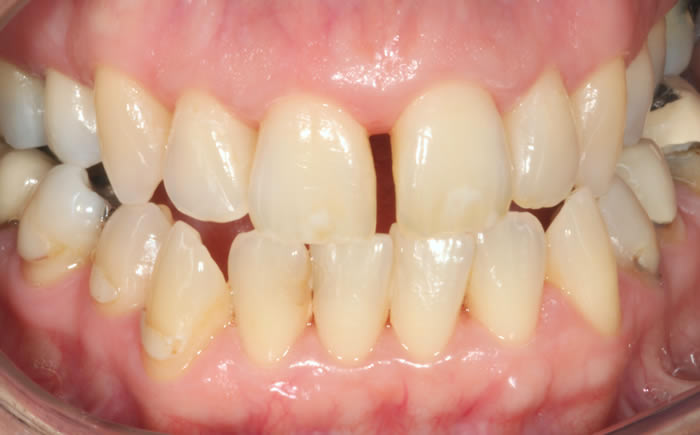

Gum disease

Case One (2 images)

Treatment of severe gum disease.

Case Two (2 images)

Treatment of moderate gum disease.